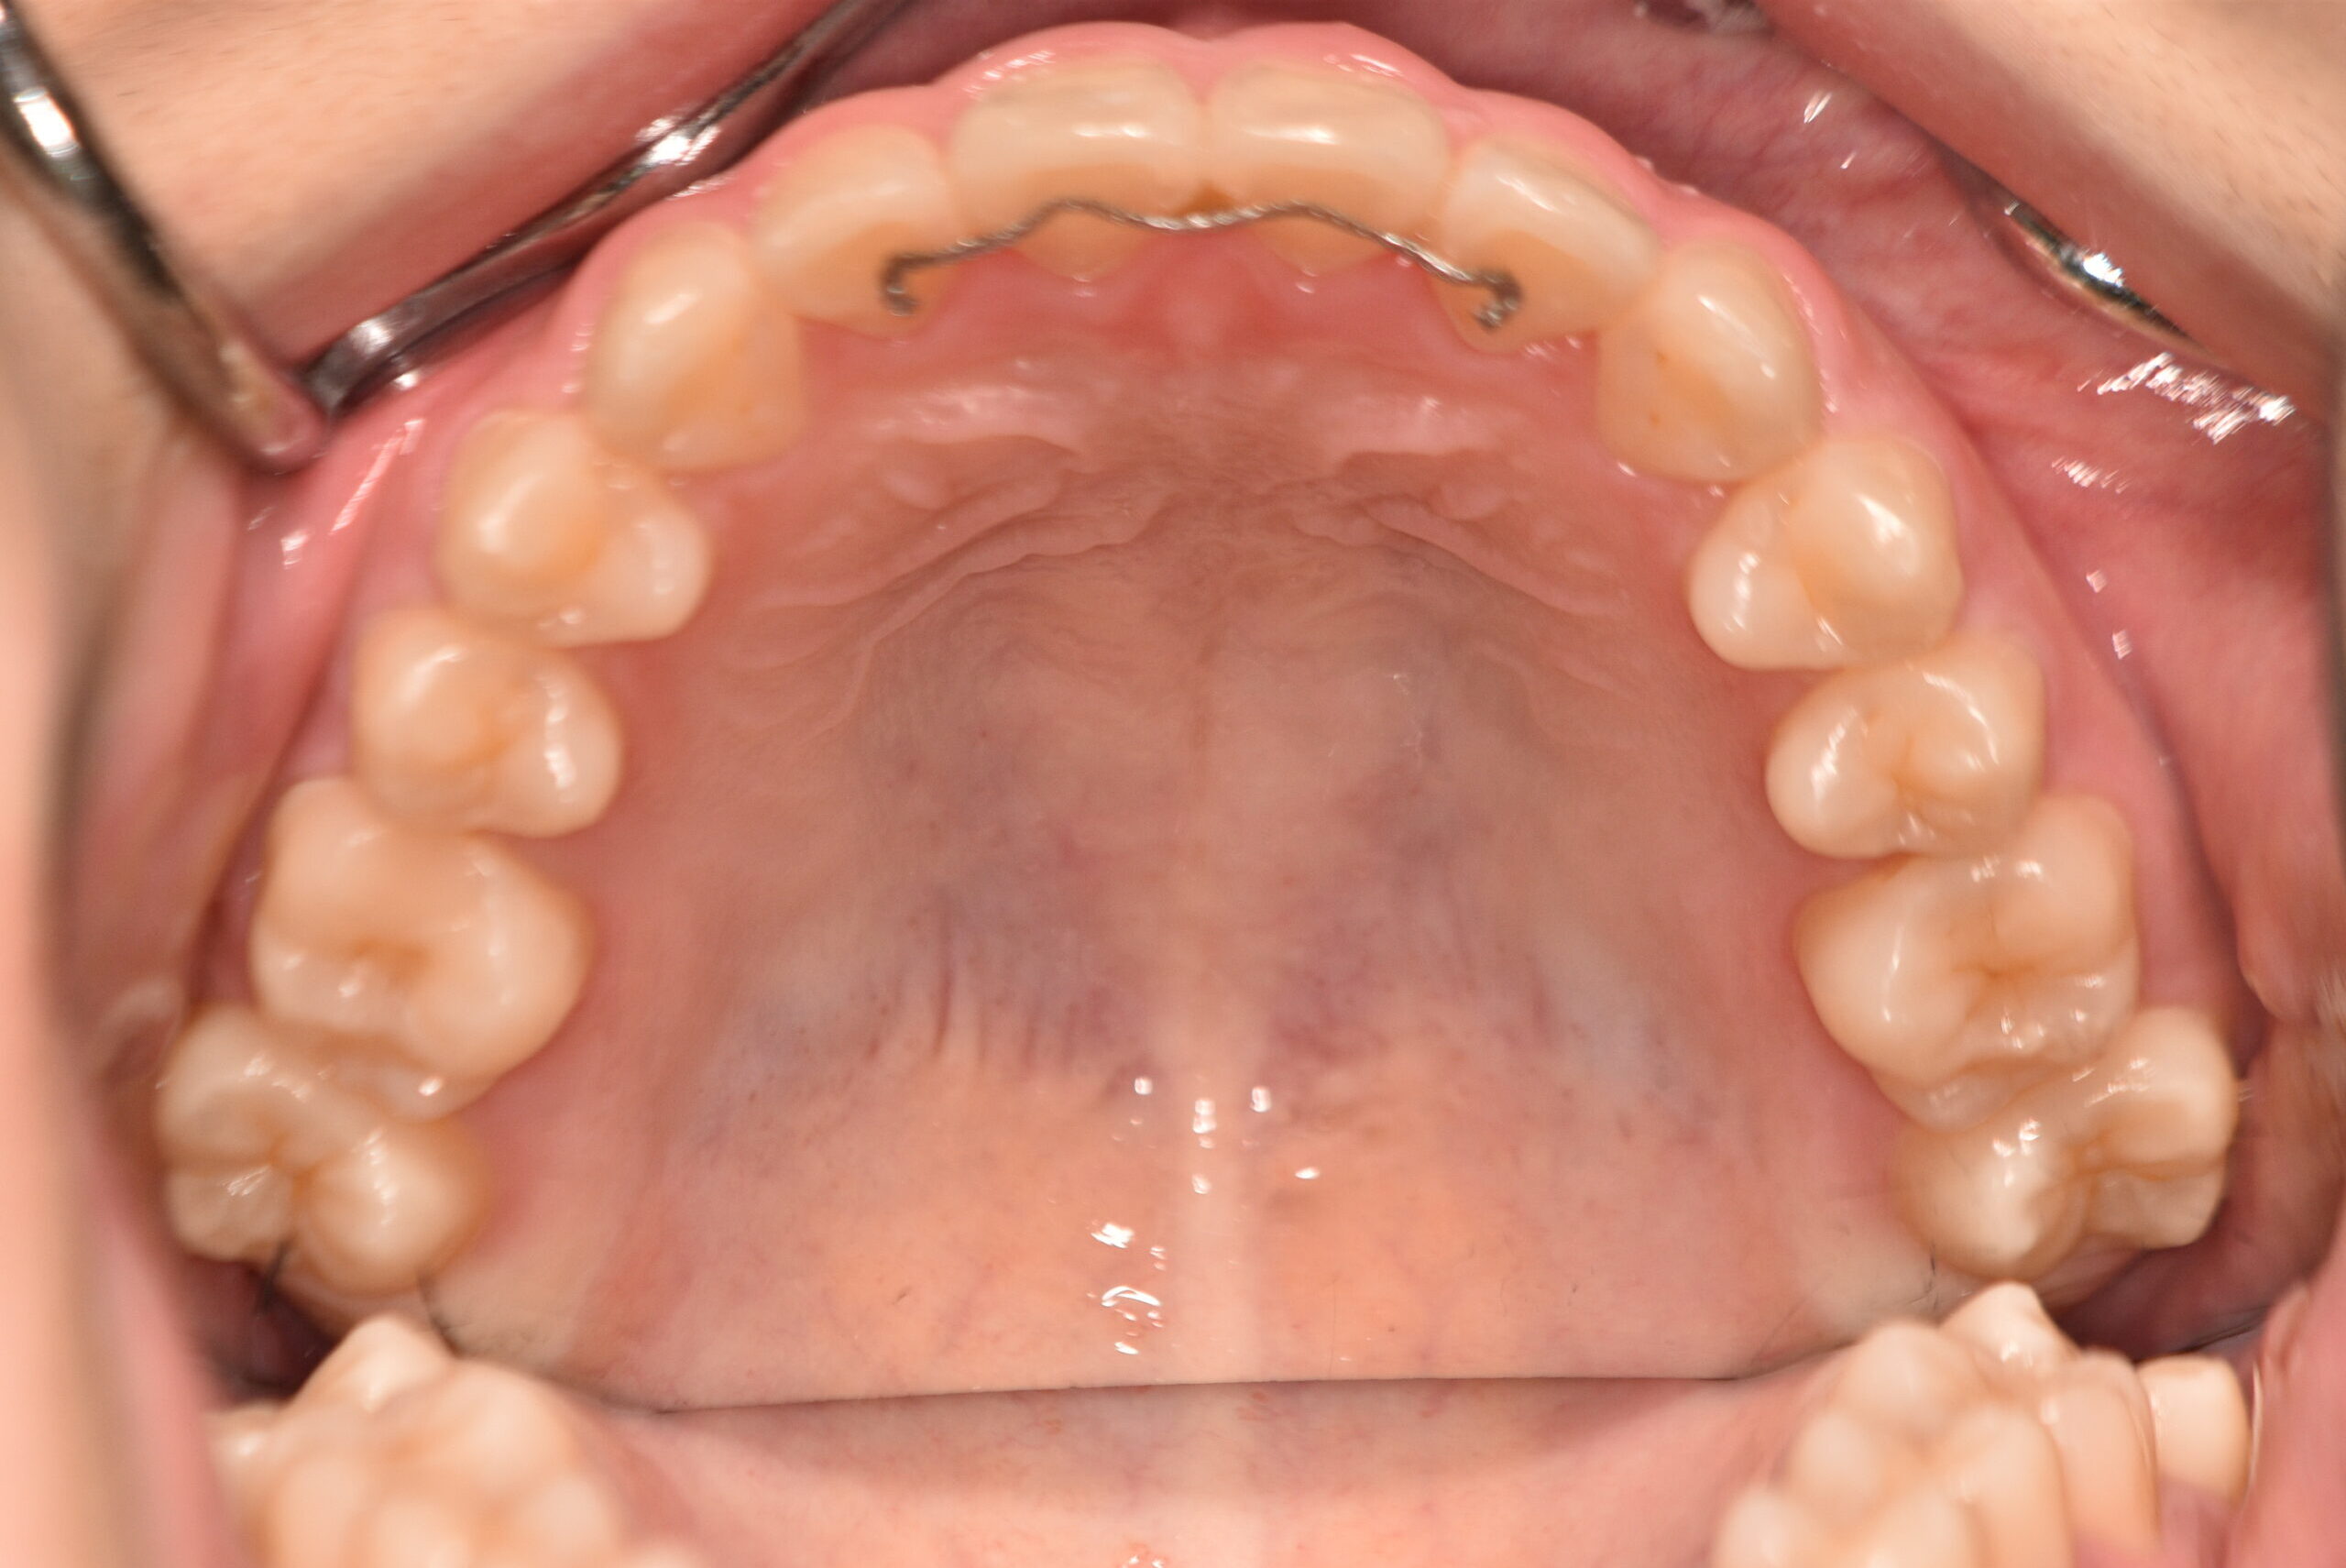

初診時

年齢

8歳8ヶ月 性 別 女性

治療期間 4年3ヶ月 費 用 矯正施術料:800,000円 調整料:4,000円/月

治療内容の詳細 初診時8歳の女性で、下顎が出ていると歯科医からの指摘を気にされ来院されました。

検査の結果、反対咬合を伴うアングルⅢ級不正咬合と診断しました。

治療としては、初期段階の治療として、リンガルアーチを使用して上顎前歯部を前方へ移動させ、反対咬合の改善を行いました。また、機能的矯正装置で鼻呼吸の獲得と舌の位置や口唇の閉鎖といった筋機能習癖の改善を行いました。